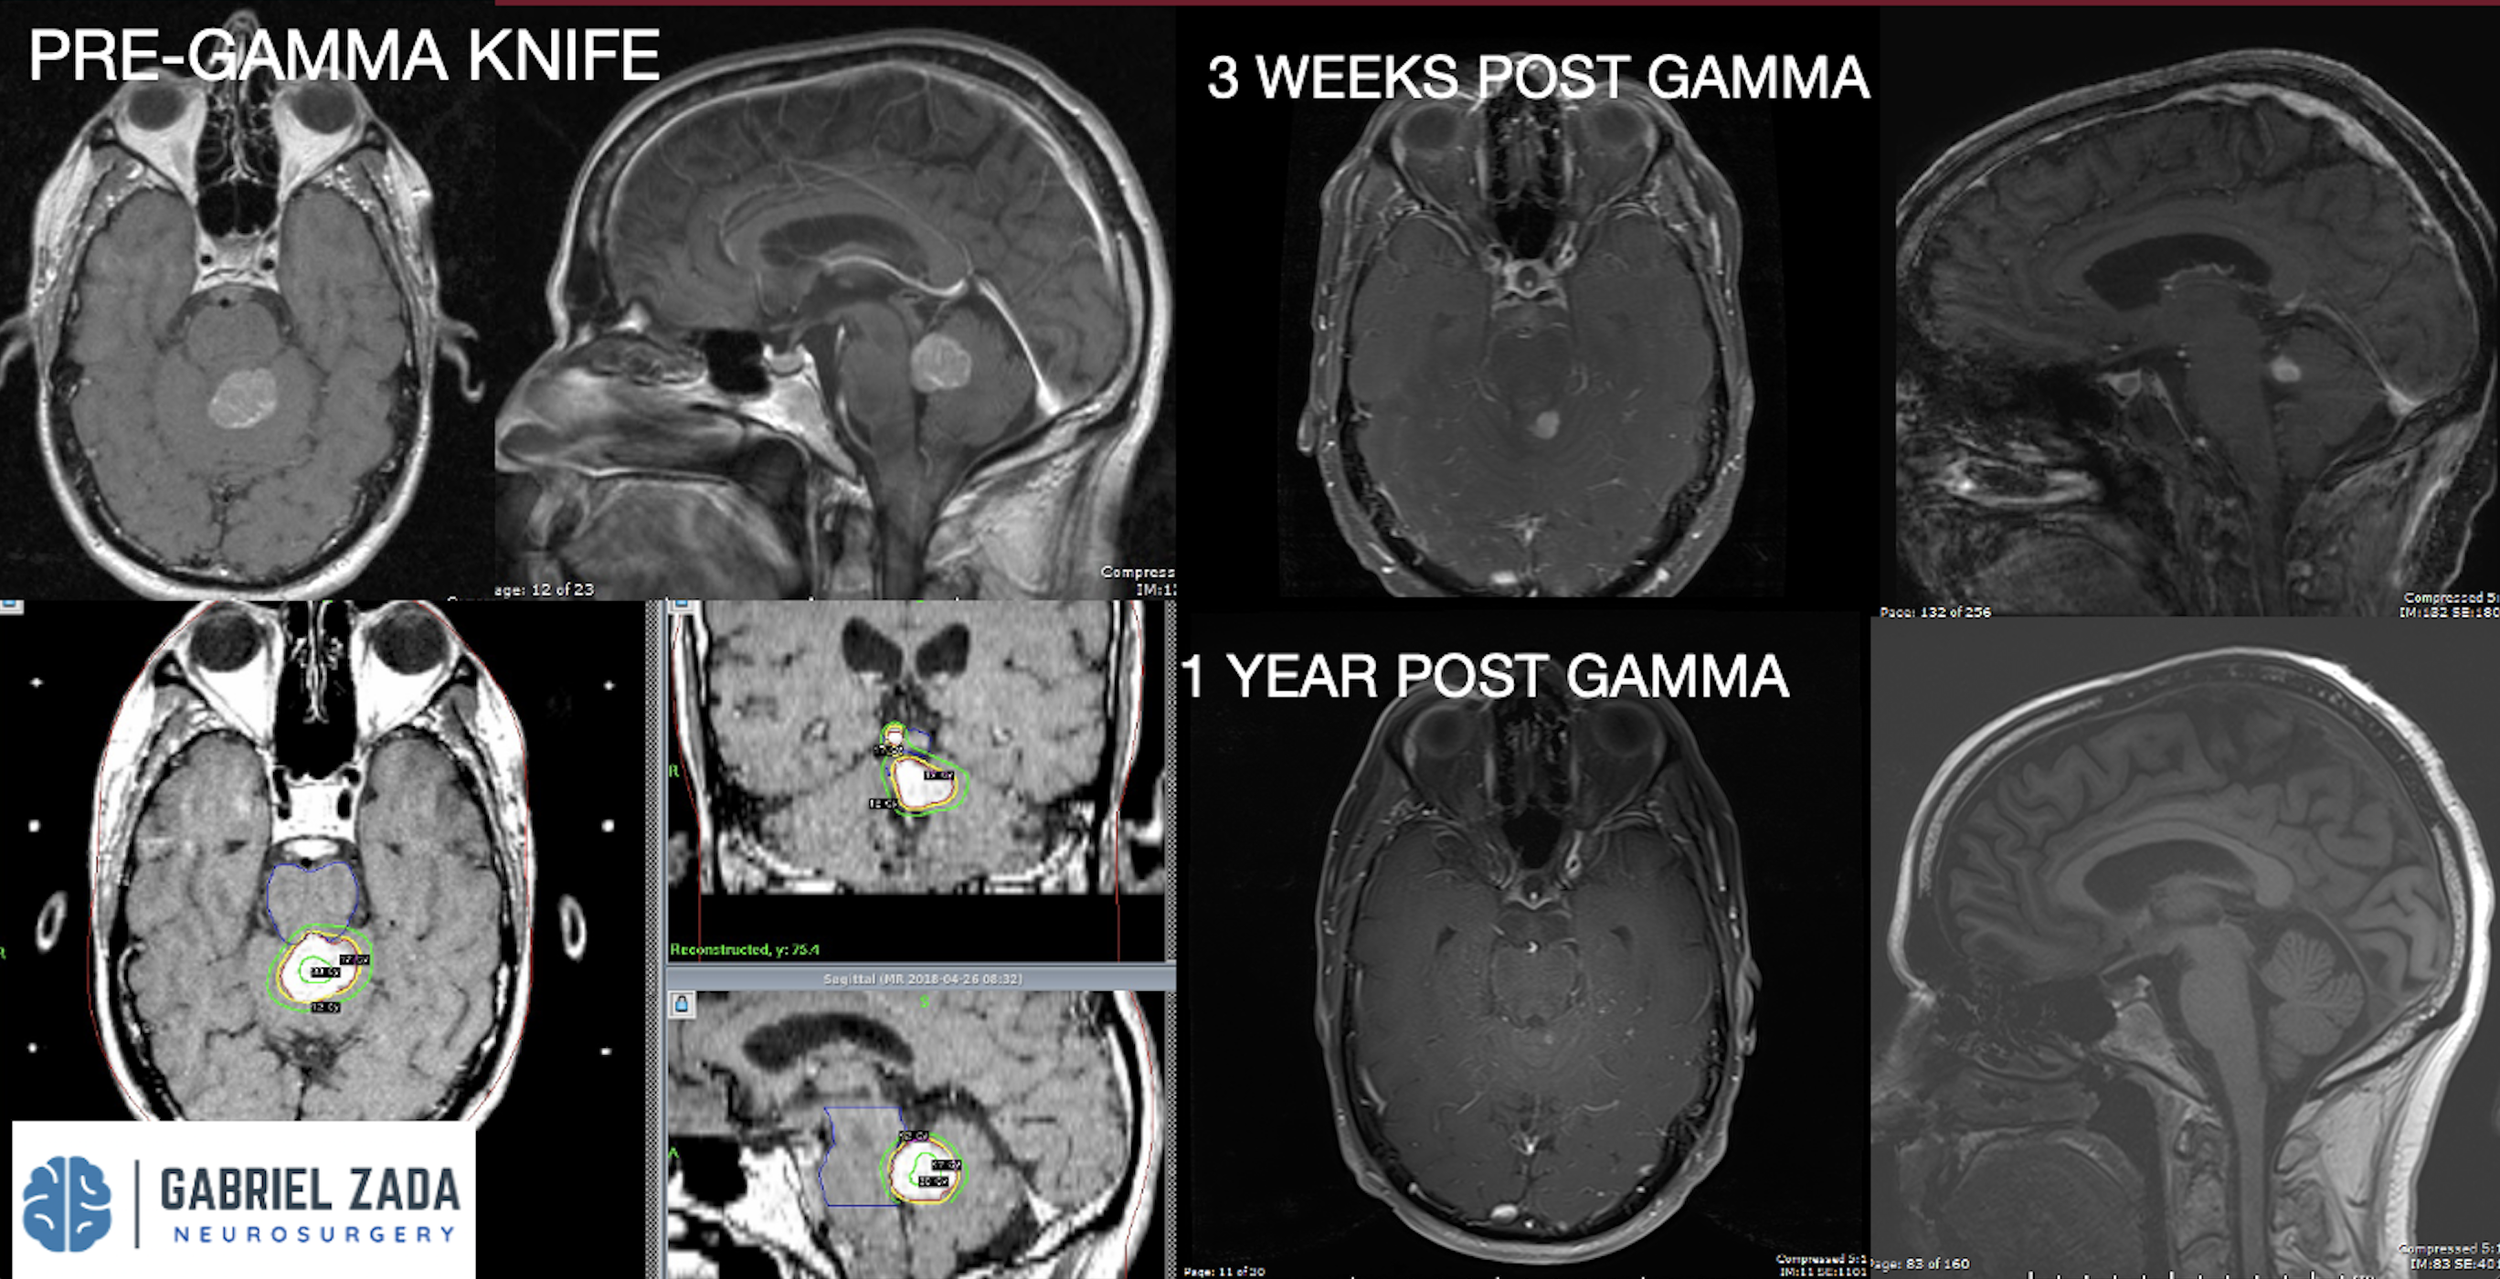

Explore this comprehensive gallery featuring pre‑ and post‑operative imaging of patients with skull‑base tumors treated by Gabriel Zada, MD, MS, FAANS, FACS. These cases highlight Dr. Zada’s expertise in advanced neurosurgical techniques and outcomes.

*Representative cases shown for educational purposes. All images de-identified. Individual results vary.